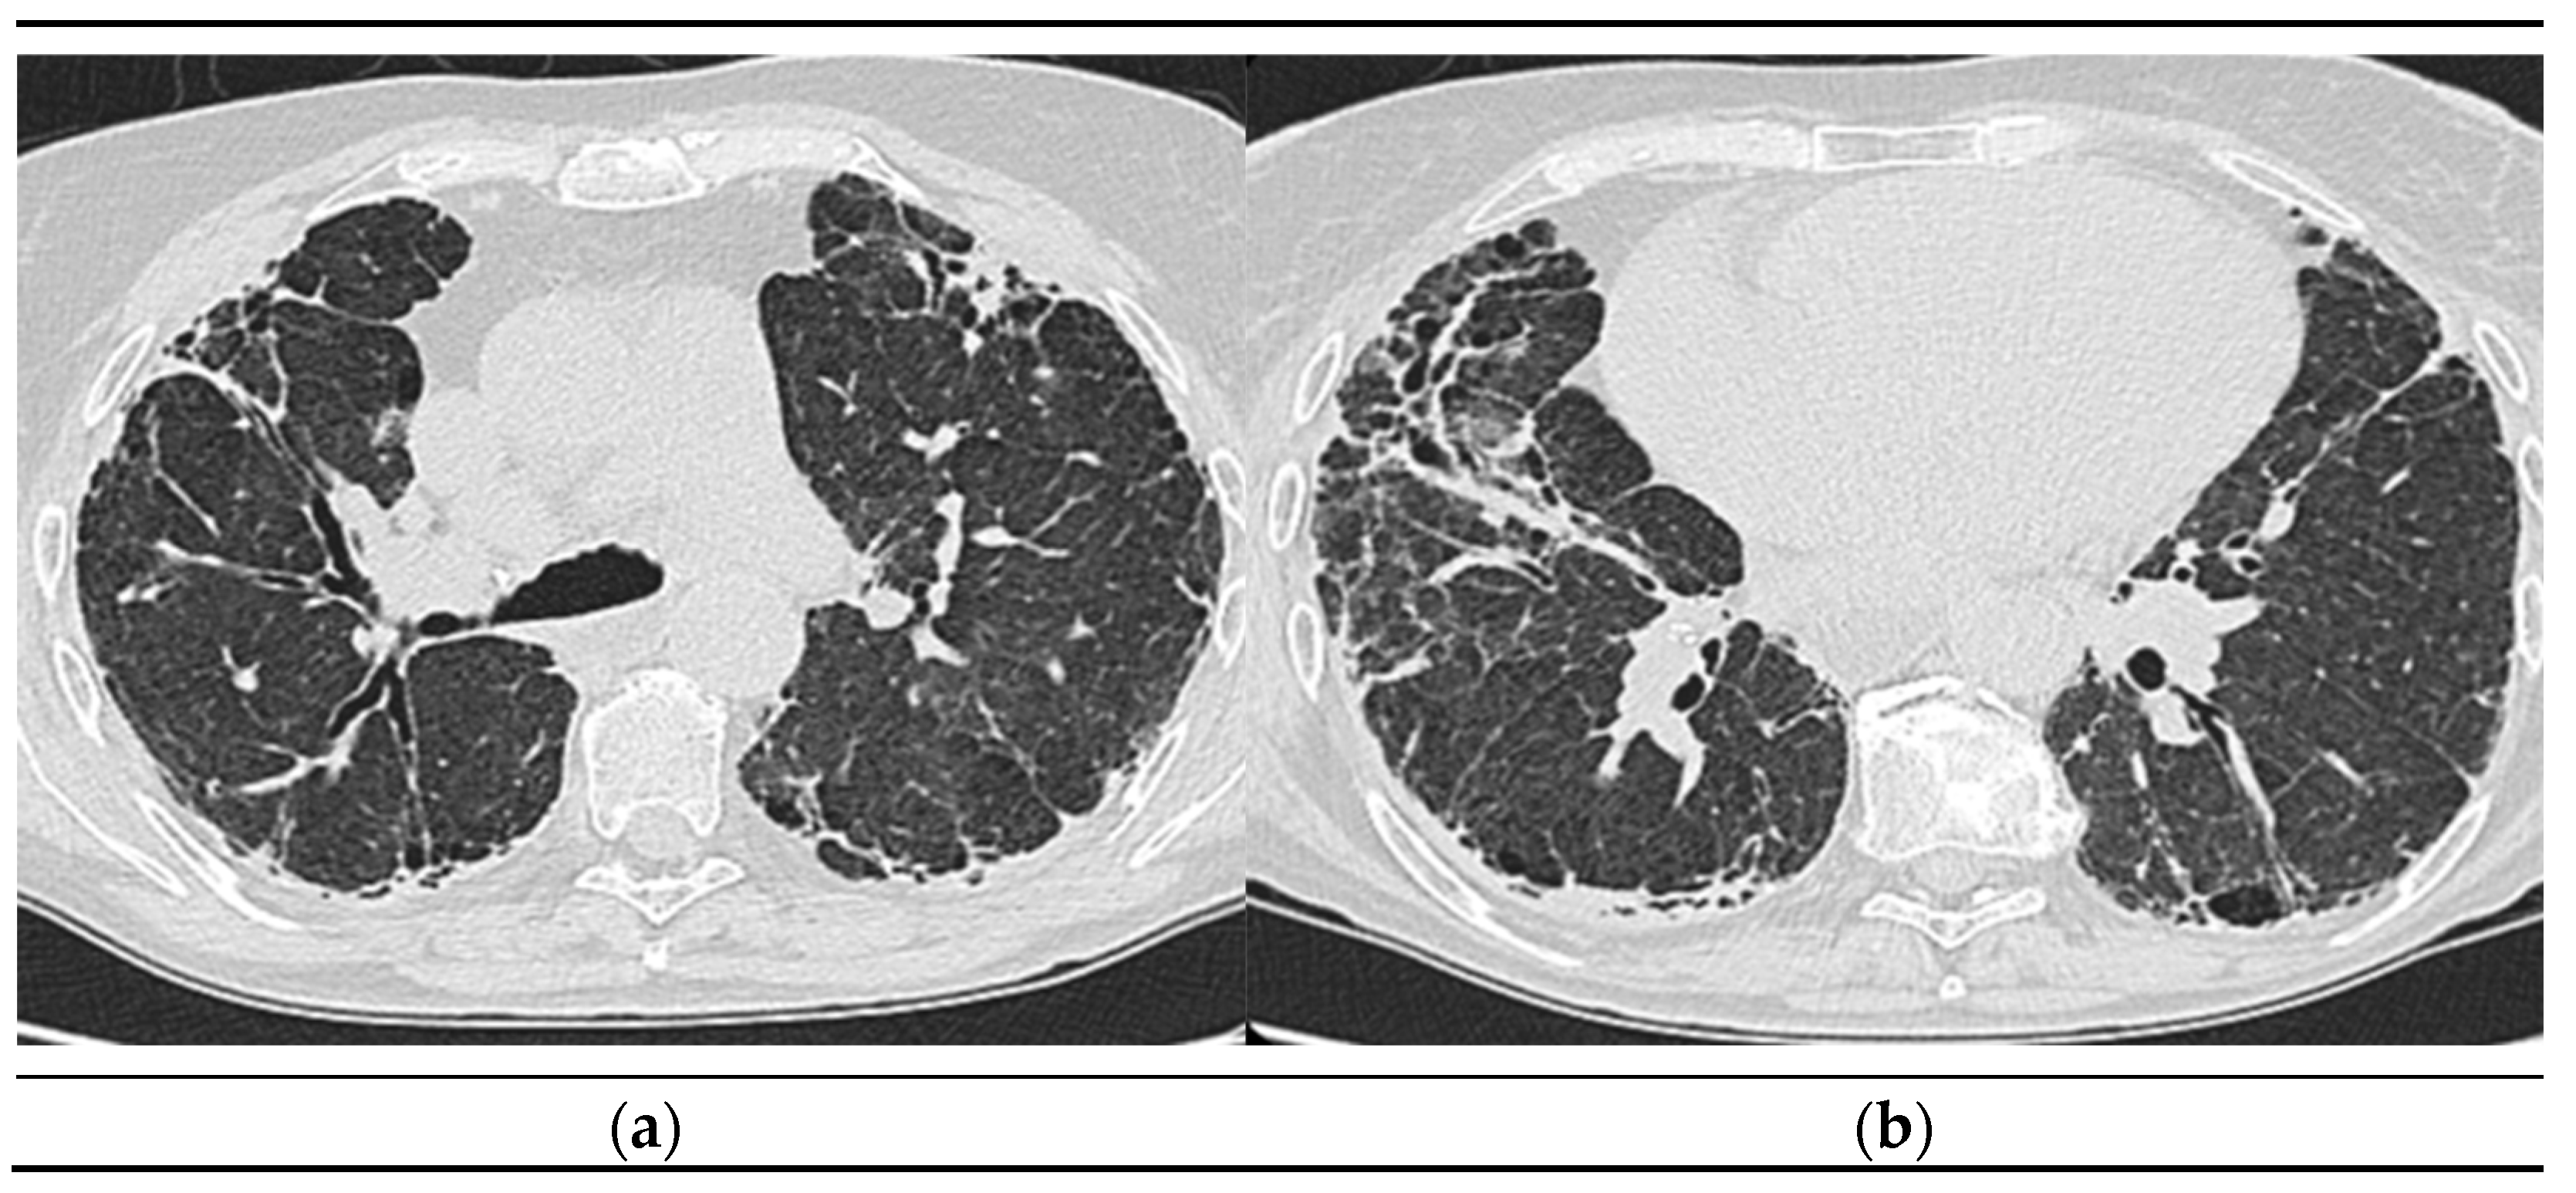

2.1.10. High-Resolution Computed Tomography (March first 2023) (Figure 3)

Predominantly subpleural reticular lesions, with a four-cornered appearance, associated with minimal right anterobasal peribronchovascular extension. Traction bronchiectasis is associated with the reticular beaches above. Subpleural areas of honeycombing more are accentuated in the lower half of the lung. Discrete peripheral organizing masses, especially the left posterior. Fibrous bands with small associated calcifications. The pleural contour is irregularly marked, with numerous spicules on the contour. The esophagus is markedly dilated along its entire length, with a caliber of up to 26 mm, regular walls, liquid stasis in the lower half. Circumferential pericarditis in a small amount. Global cardiomegaly. The pulmonary artery cone has a caliber of 36 mm, in the context of known pulmonary hypertension. Numerous supracarinal bilateral mediastino-hilar adenopathies, some of them with small calcifications, with an inflammatory appearance. Thyroid with normal position and dimensions, inhomogeneous, micropolynodular structure. Conclusions: The CT appearance is an appearance of interstitial lung pneumopathy progressive fibrosing phenotype, examination quasi-identical to the previous CT examination. Dilated pulmonary arteries with the appearance of PAH. Minimal pericarditis. Cardiomegaly. Polynodular goiter. Dorsal spondylarthrosis.

Considering the underlying pathology, progressive systemic sclerosis and interstitial lung disease, the next step in the diagnostic algorithm was progressive evaluation. The restrictive pattern expressed on body plethysmography associated with a significant decrease in DLCO, the clinical deterioration of the patient, and the progression of imaging lesions on HRCT led to the classification of the patient as having an SSC-ILD progressive phenotype.

Figure 3. a), b): Reevaluation of Lung Tomography.